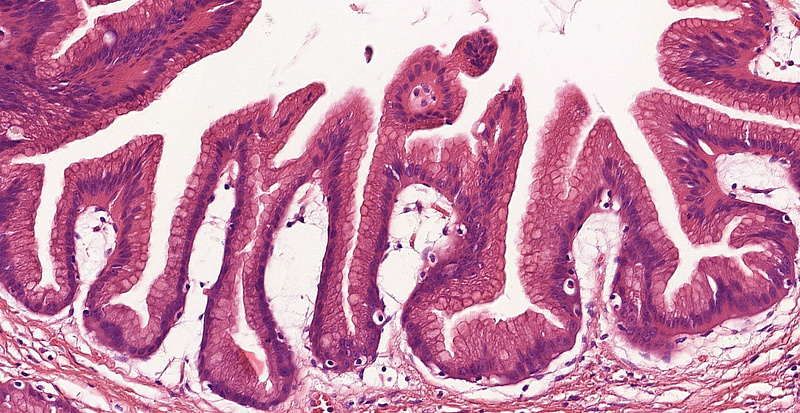

The operation specimen showed a well-circumscribed, multilocular, cystic lesion measuring 35 mm in largest dimension. Microscopic examination showed intraductal / intracystic papillary proliferations. The cells were reminiscent of gastric foveolar epithelium with apical mucin cap and mild atypia. Focal oncocytic change was also visible. Ovarian-like stroma was not detected. Intestinal or pancreatobiliary differentiation as well as invasive components were not identified (Panels A-C).